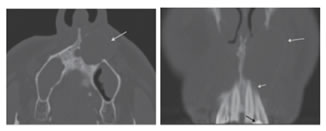

4. Ameloblastoma: Ameloblastoma is the second most common benign odontogenic tumor and shares a tendency for being locally aggressive and having a relatively high recurrence rate. Ameloblastoma represents 11% of the tumors of the maxillofacial region. It is the commonest and most clinically significant odontogenic tumor. It arises from odontogenic epithelium. It has multiple histological types which are difficult to differentiate radiologically. The commonest regions to be affected are the molar area and ascending ramus.16 There are a number of histologic subtypes of ameloblastoma, with the multicystic and unicystic follicular types most common; the less common desmoplastic, plexiform, and a canthomatous variants are generally indistinguishable on conventional imaging. Ameloblastomas are mixed cystic and solid lesions with the multi-cystic lesions generating the more classically known “bubbly” appearance produced by multiple intralesional septations (Fig. 10 A); with contrast administration, these septations will typically enhance. The unicystic variants may contain a mural nodule that likewise enhance; identification of a mural nodule is key to differentiating this variant from the KCOT or the dentigerous cyst (Fig. 10 B). Differentiation from a KCOT and other odontogenic lesions is very hard by plain x-rays and CT, and the differential diagnosis should be considered. The ameloblastoma leads to marked buccolingual jaw expansion and resorption of the roots than a KCOT.16 The less common subtypes may have more aggressive appearing features, or like the desmoplastic subtype, may appear in more anterior alveolar locations (Fig. 10 C).17 On MRI, the cystic elements will beT2 hyperintense, which helps to distinguish them from other benign mesenchymal odontogenic or malignant neoplasms. Moreover, although these lesions will appear cystic, the ameloblastoma is a more cellular lesion than the KCOT and thus the solid elements will generally restrict diffusion to a greater degree. MRI features of ameloblastoma offers accurate diagnosis. They include multilocularity, mixed cystic and solid components, irregular thicken wall, papillary projections, and mural and septal enhancement.12,15

10

Figure10: Ameloblastoma. (A) Axial bone CT shows the multi-septated or loculated appearance of the multicystic ameloblastoma. Also, it shows course septations and the eccentric expansion (arrow). (B)Axial contrast-enhanced CT of a unicystic ameloblatoma demonestrates a cystic lesion eccentrically expanding the buccal and lingual cortices. The enhancing mural nodule (arrow) is a characteristic feature for ameloblastoma. (C) Axial bone CT of a desmoplastic type of ameloblastoma. The expansile lobulated and loculated mass (long arrow) is

characteristic for ameloblastoma; the more anterior location is less common. However, the location, aggressive sclerotic changes and periosteal reaction (short arrow) are seen more often in this type.